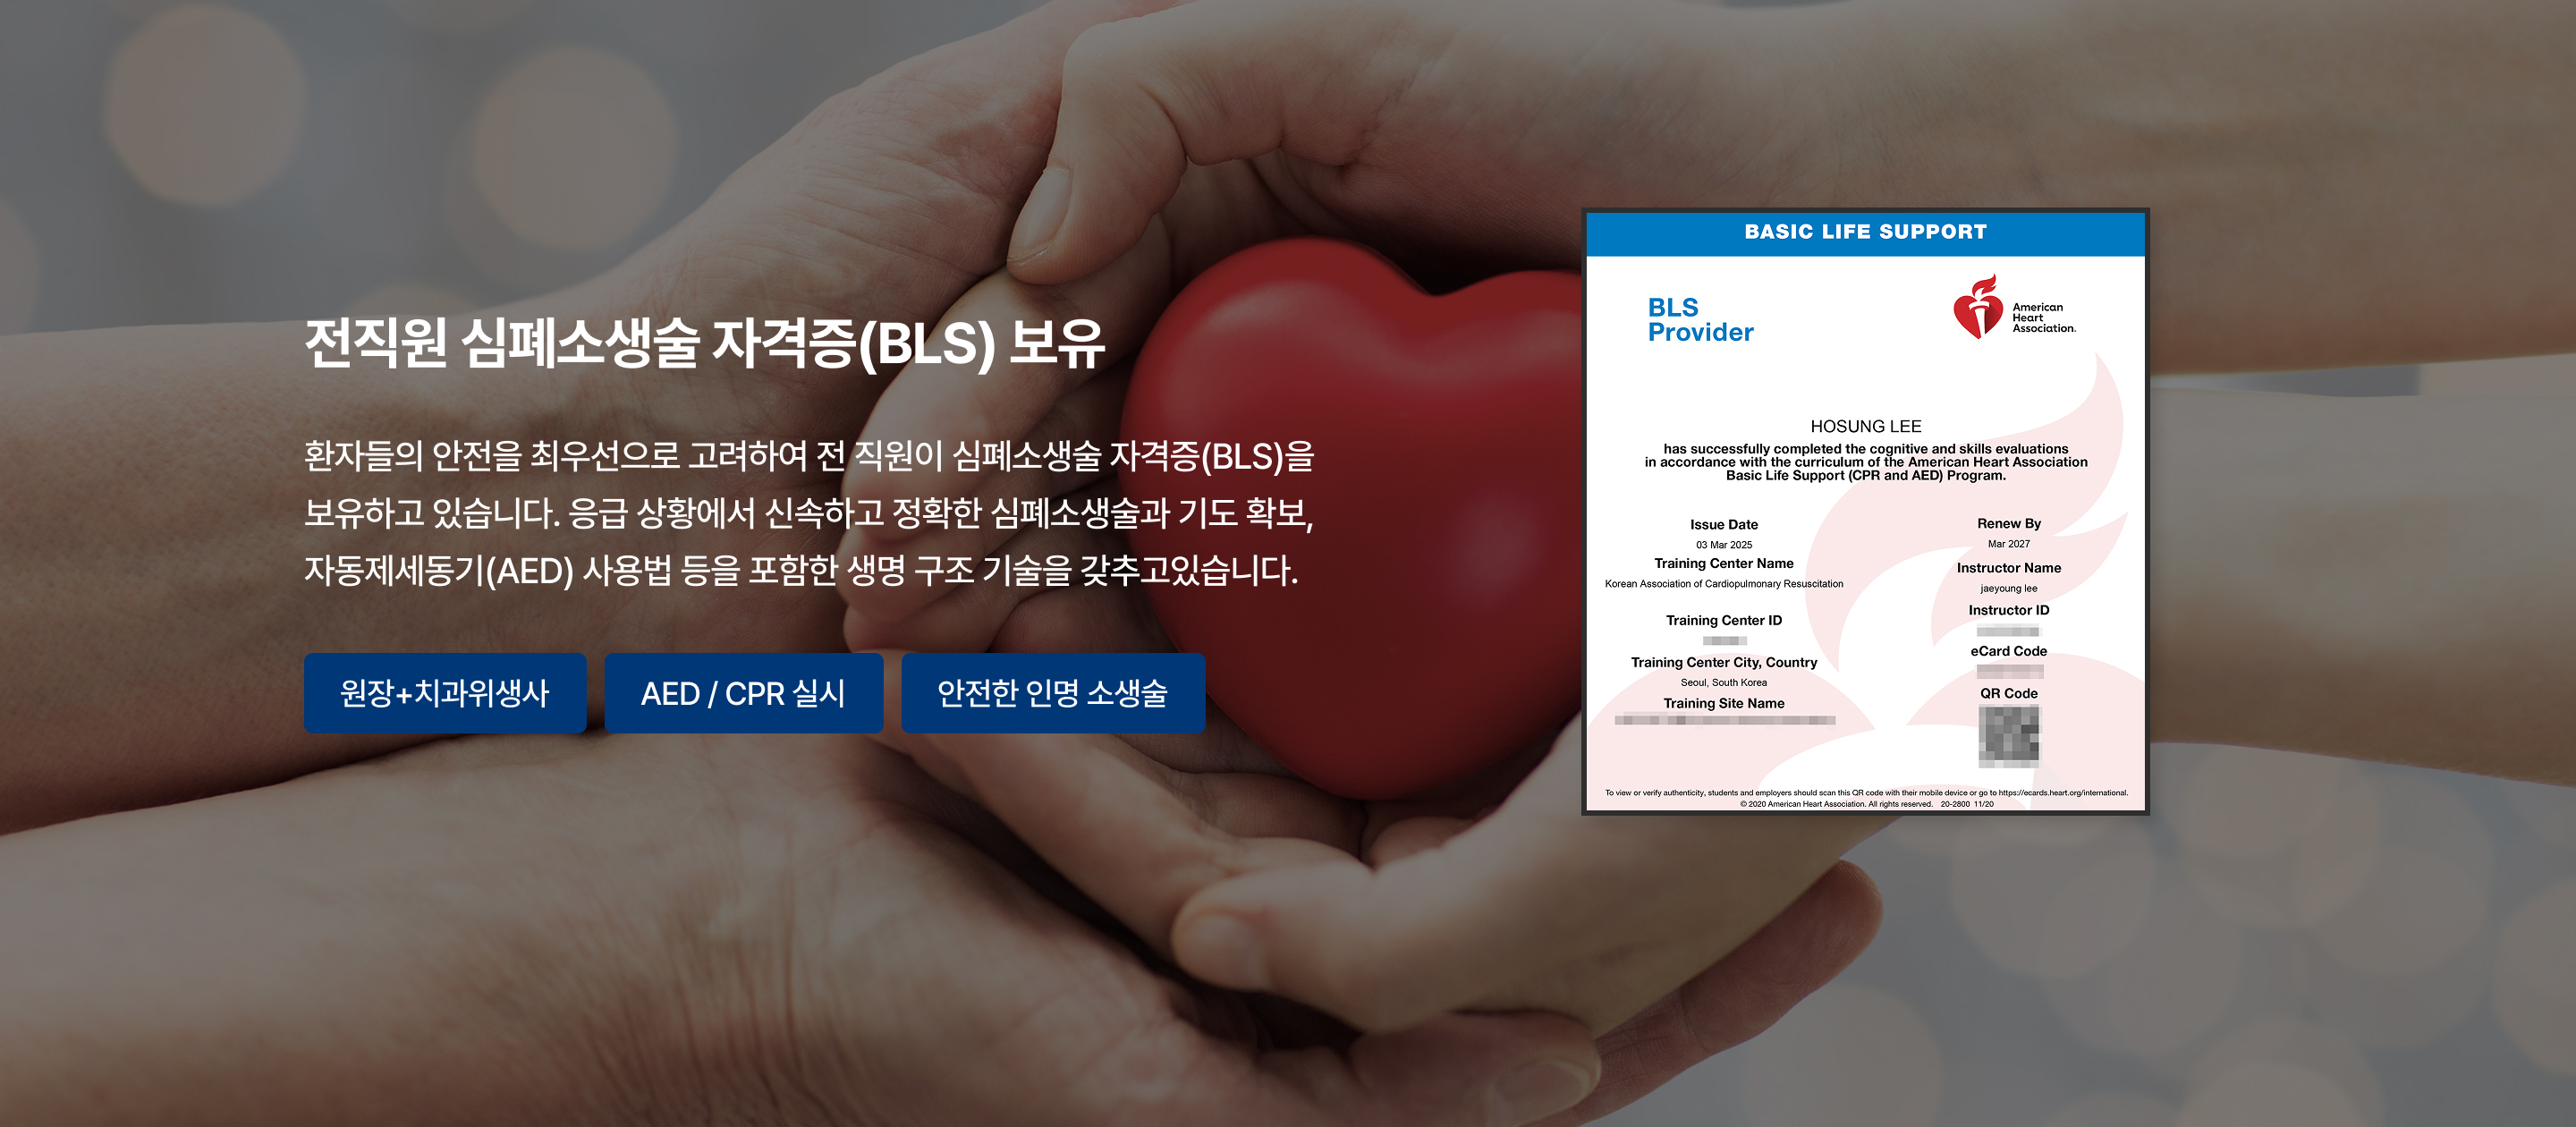

심폐소생술 자격증 보유